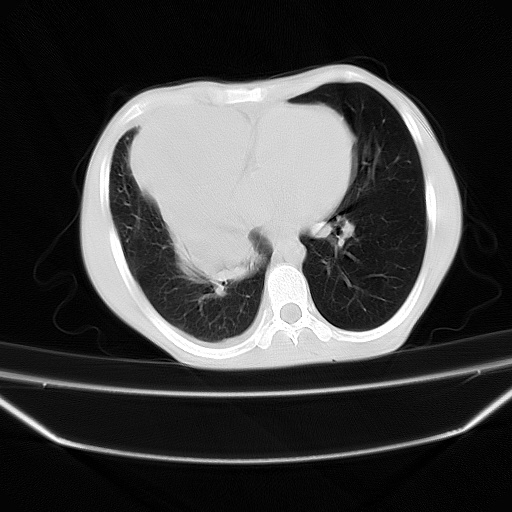

以下是引用zjzjr在2008-7-20 12:57:00的发言:[br]考虑为生殖源性肿瘤(内胚窦瘤),侵袭性胸腺瘤可能性大;右侧少量胸腔积液。

以下是引用xinliheng001在2008-7-20 21:17:00的发言:[br]右纵隔巨大分叶状软组织均质密度肿块,右上肺叶受压明显,纵隔右移、胸膜受累有少量积液和结节样增厚。应增强扫描一定会有更具诊断价值的信息。

以下是引用xinliheng001在2008-7-20 21:17:00的发言:[br]右纵隔巨大分叶状软组织均质密度肿块,右上肺叶受压明显,纵隔右移、胸膜受累有少量积液和结节样增厚。应增强扫描一定会有更具诊断价值的信息。